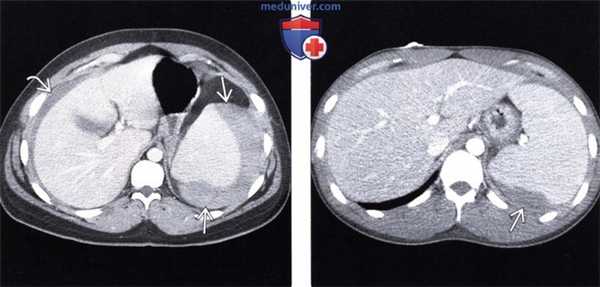

(Слева) Аксиальная КТ с контрастом у пациента с мононуклеозом: визуализируется свернувшаяся кровь вокруг увеличенной селезенки («сторожевой» сгусток) и внутрибрюшное кровоизлияние низкой плотности (гиподенсное). В данном случае спонтанный разрыв селезенки не потребовал оперативного вмешательства.

(Справа) При аксиальной КТ с контрастным усилением у пациента с мононуклеозом была выявлена гематома по краю селезенки, возникшая в результате ее разрыва. В этом случае пациенту также не потребовалось оперативное лечение. (Слева) При аксиальной КТ без контрастного усиления выявлена увеличенная селезенка с прилежащей к краю органа гиперденсной гематомой («сторожевой» сгусток) и свободная гиподенсная кровь в брюшной полости.

(Справа) При аксиальной КТ с контрастным усилением у пациента с мононуклеозом была выявлена гематома по краю селезенки, возникшая в результате ее разрыва. В этом случае пациенту также не потребовалось оперативное лечение.

(Слева) При аксиальной КТ без контрастного усиления выявлена увеличенная селезенка с прилежащей к краю органа гиперденсной гематомой («сторожевой» сгусток) и свободная гиподенсная кровь в брюшной полости.